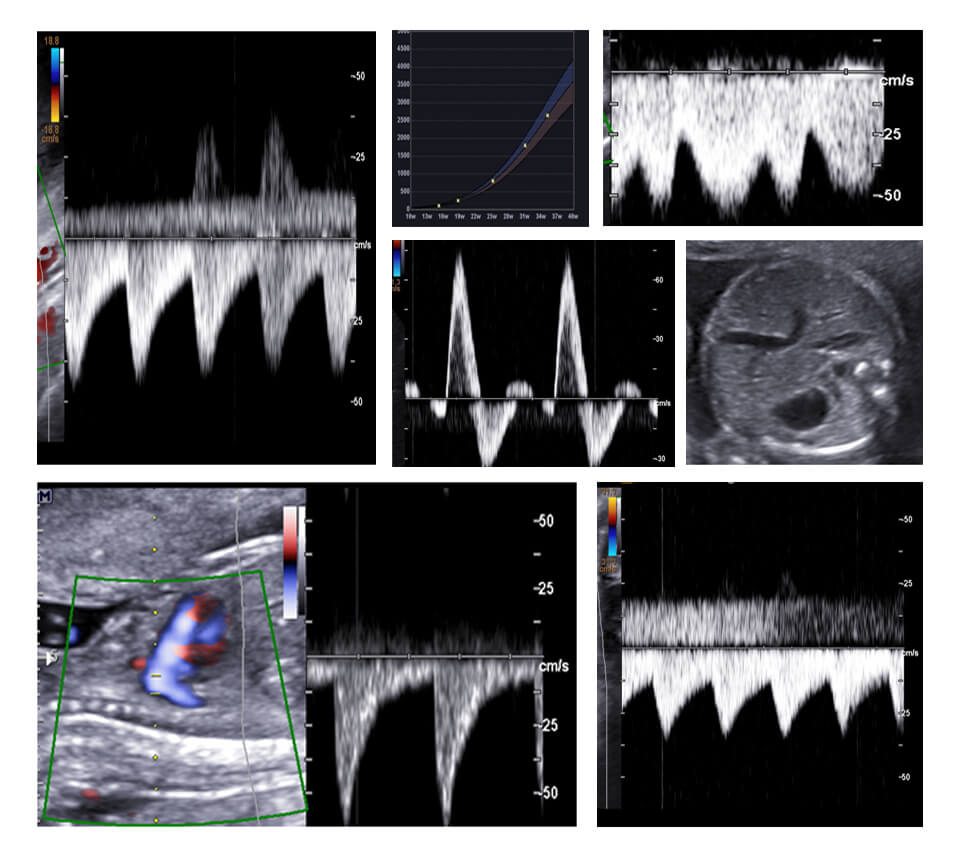

MODULE 8 :- BIOMETRY & COLOR DOPPLER

FETAL BIOMETRY/ FGR CONCEPTS/ IMPORTANCE OF GRAPHS AND SERIAL EVALUATION, COLOR DOPPLER : UTERINE/ UMBILICAL/ MCA/ DUCTUS/ CPR, TO SCREEN/ TO MANAGE/ TO PROCEED OR TERMINATE